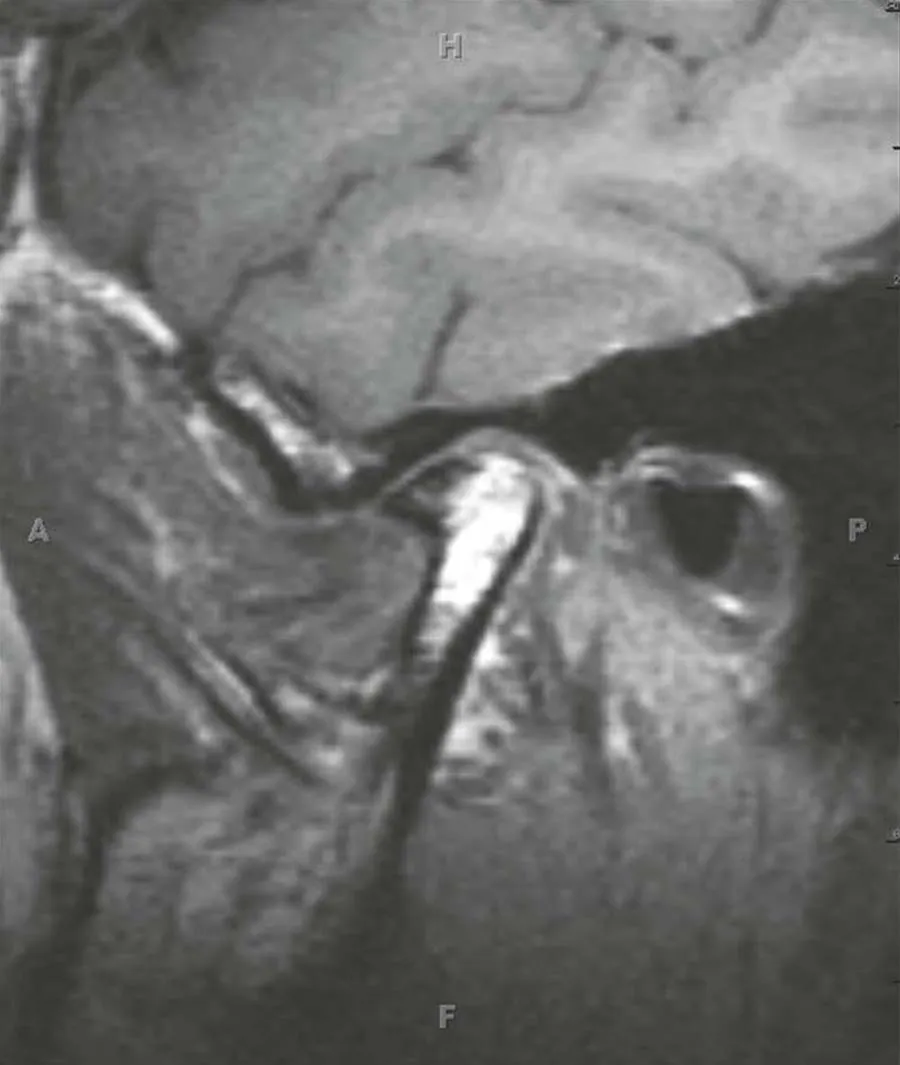

Incorporate today's most advanced imaging techniques with the new 4th edition of Head and Neck Imaging! A bestselling volume in the popular Case Review Series, this updated reference helps speed your differential diagnoses and ensure your proficiency, in addition to serving as a study guide for general radiology and neuroradiology subspecialty examinations, certificates of added qualification, and radiology/neuroradiology recertification. The all-inclusive volume can serve as a comprehensive review of the subspecialty and as a primer for excelling at the Head and Neck Tumor Boards.- Efficiently study and review with help from a format that mimics the General Diagnostic Radiology and Neuroradiology Board Exams. Each case begins with a differential diagnosis question and follows with multiple-choice questions, answers with rationale, and an emphasis on clinical issues.- Explore hot topics including CT and MR angiography of the neck; multi-detector CT with 3D reconstructions; post-transplant lymphoproliferative disorders; HIV infections; squamous cell carcinoma, diagnostic and therapeutic image-guided procedures; medical economics; and much more.- Master the latest techniques with 150 new and 50 updated head and neck cases and over 800 images focusing on differential diagnosis, tumor staging, treatment options, and resectability issues.- Enhance your understanding with multiple-choice questions accompanying each case, emphasizing cranial nerves, skull base lesions, sinonasal, orbital, salivary gland, aerodigestive system mucosal lesions and deep space neck masses.- Utilize convenient cross-references to recent articles.- Stay abreast of the most recent discoveries in HPV (+) squamous cell cancers, high-resolution imaging, and CTA, MRA, and CISS applications.- Explore the differential diagnosis and/or anatomic details of every case presented.- Understand the surgical and radiation therapy considerations for cosmetic and functional outcomes.- Expert Consult eBook version included with purchase. This enhanced eBook experience allows you to search all of the text, figures, and references from the book on a variety of devices.